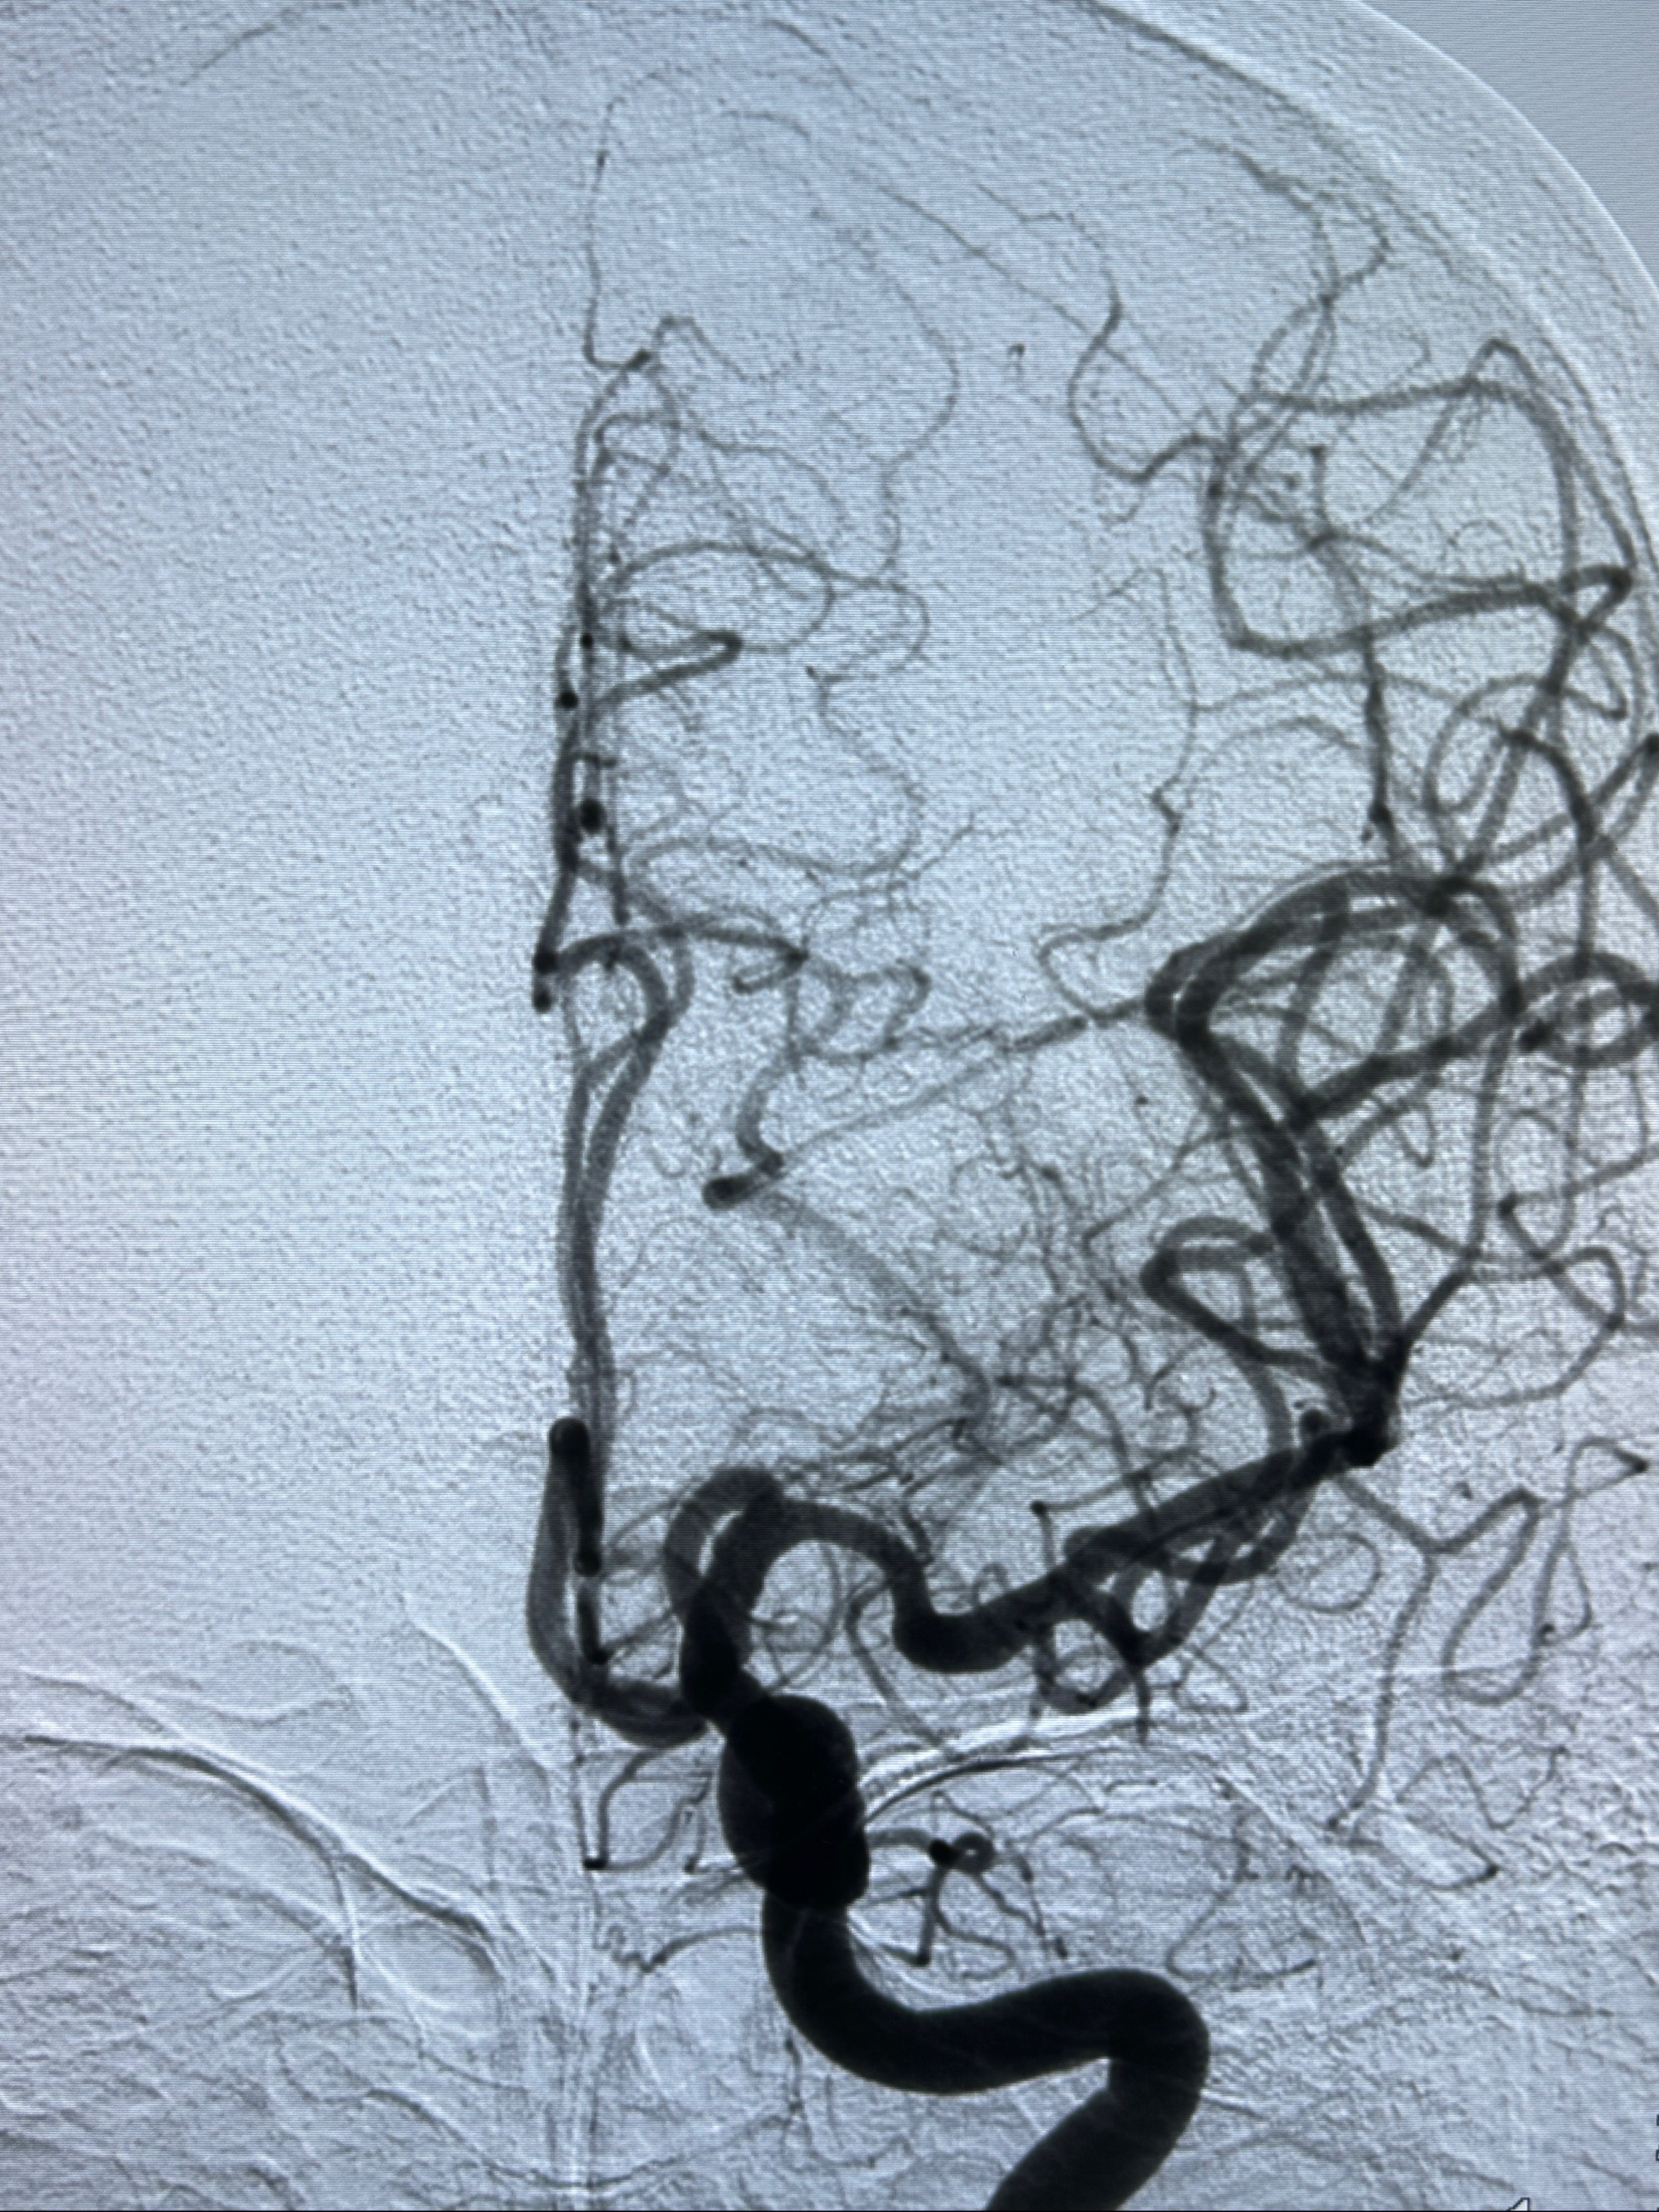

2023-11-24DSA:右侧大脑中动脉下干起始部动脉瘤,约2.3*2.5mm,形态规则

治疗策略:

- 随访?

- 夹闭?

- 单弹簧圈填塞?

- 支架辅助治疗?